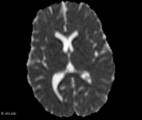

Diffusion-weighted images (DWI) and Diffusion Tensor Imaging (DTI) are well-known and powerful imaging techniques in MRI. For DTI images, the most used measurements are the fractional anisotropy (FA) and apparent diffusion coefficient (ADC). However, the limitations of FA and ADC formalism are also vastly debated due to low tissue contrast for ADC maps and measurement artifacts present in crossing-fiber orientation for FA maps. Although the DTI evaluation has evolved continually in recent years, there are still struggles regarding the quantitative measurement that can benefit brain areas that are consistently difficult to measure on diffusion-based methods, e.g., the grey matter (GM). The present Slicer extension proposes offer an image processing technique using the principle of diffusion distribution evaluation regarding the LMC complexity measure, named Diffusion Complexity (DC). [1].

- DC map has a signal peak in GM tissue, which can be important to discriminate brain diseases in this particular brain tissue that is challenging to other classical DTI maps (e.g. FA and ADC)